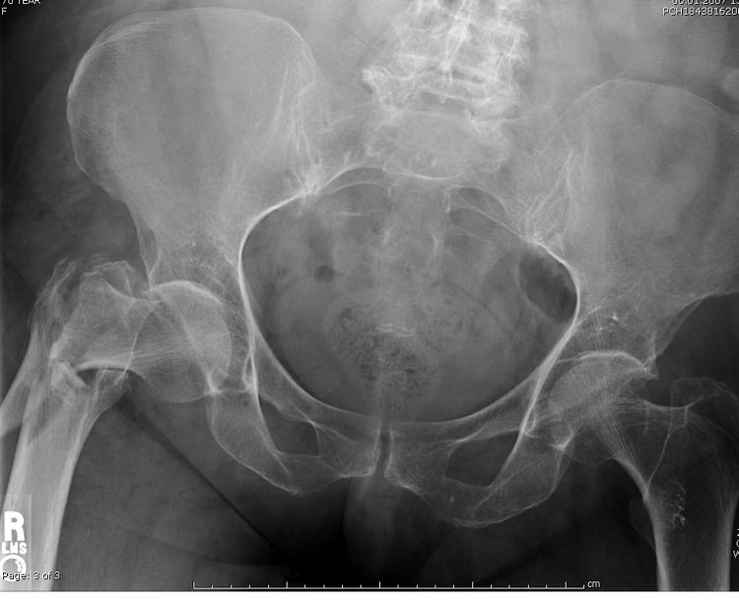

Здесь пара случаев фиксации похожих переломов:

первый высокоэнергетическая травма 36 лет